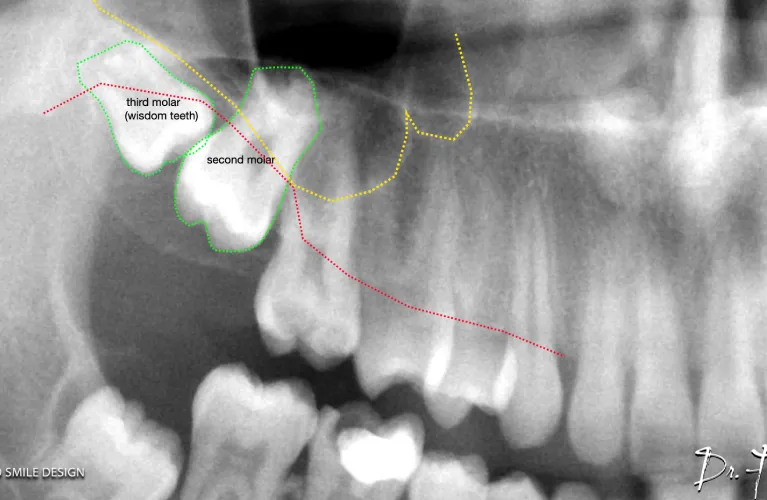

Pre-Operative Xray Required

OPG

CBCT